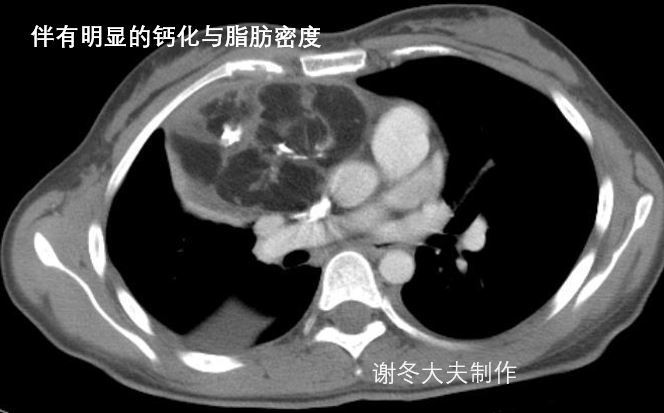

4.谢大夫,这个前纵隔占位,是胸腺瘤吗?

回答:这是一个纵隔畸胎瘤,不是胸腺瘤,这个肿瘤内部包含很多脂肪成分,以及钙化影,这些都是典型纵隔畸胎瘤的表现